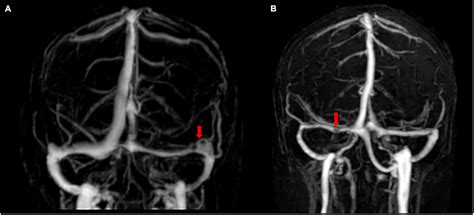

Magnetic Resonance Venography (MRV) Uses magnetic resonance imaging to visualize the venous sinuses and detect any abnormalities.

Computed Tomography Venography (CTV) Uses computed tomography to create detailed images of the venous sinuses.

Digital Subtraction Angiography (DSA) Provides a detailed view of the blood vessels and can help identify the exact location and extent of the stenosis.

These imaging tests are crucial for confirming the diagnosis and planning appropriate treatment.